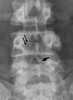

Compensatory hypertrophy with contralateral neural arch deficiency

Enlarged vertebral pedicle